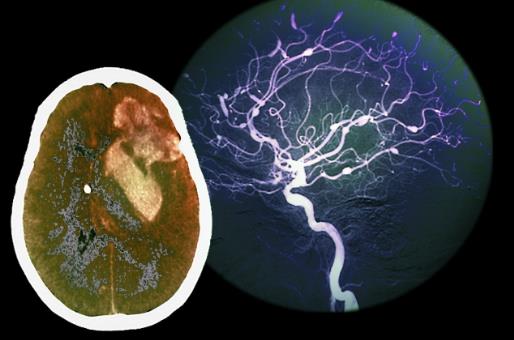

大脑:20岁开始衰老

随着我们年龄越来越大,大脑中神经细胞(神经元)的数量逐步减少。我们降临人世时神经细胞的数量达到1000亿个左右,但从20岁起开始逐年下降。到了40岁,神经细胞的数量开始以每天1万个的速度递减。